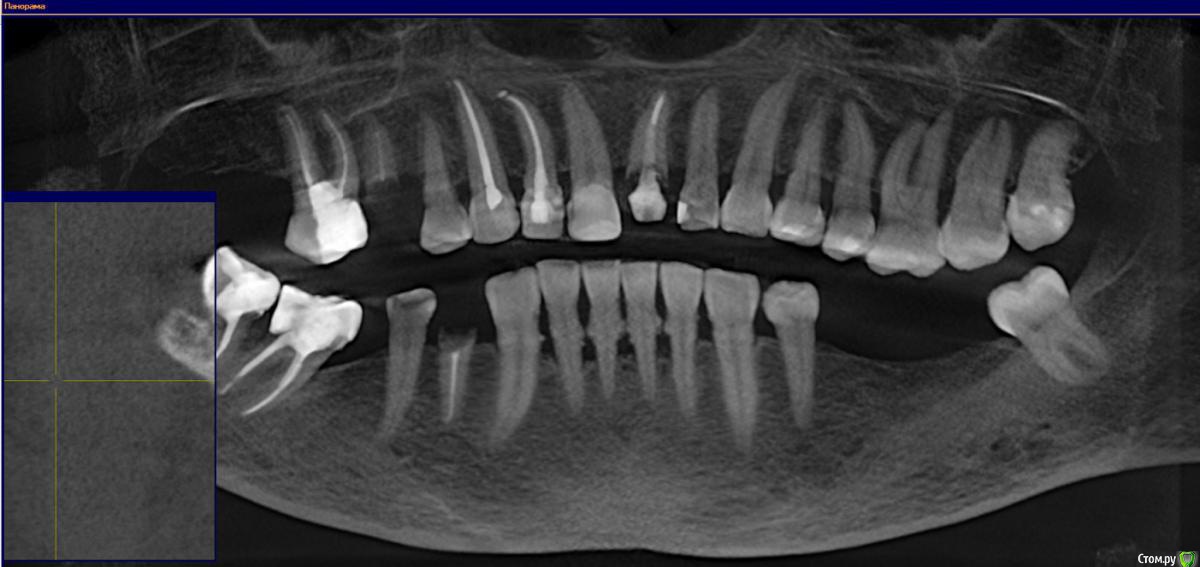

pioneer3 Опубликовано 12 апреля, 2016 Поделиться Опубликовано 12 апреля, 2016 Всем добрый день!На днях у мамы (54 года) сломался штифт в 21 зубе, терапевт попробовал его лечить, но он оказался хрупким и пришлось удалять.Заодно заметили глубокий кариес на 11, в итоге депульпировали и поставили временную пломбу. Спросили у врача насчет импланта на удаленный зуб, но - "так как соседние зубы депульпированы и считаются "мертвыми" долго они без коронок все равно не простоят", сказал что оптимальнее ставить мост - притом закрыть максимальное кол-во зубов, т.е. 5. В зону моста попадают:22 - леченый здоровый зуб21 - удален11 - депульпирован с временной пломбой12 - депульпирован со штифтом13 - депульпирован, но выглядит пока здоровым Подскажите пожалуйста:1) Действительно ли оптимальнее сейчас ставить мост?2) Закрывать ли мостом клык - 13, другой стоматолог сказал что можно с ним пока ничего не делать, но он не видел снимок?3) Что лучше - поставить "длинный" мост, или допустим на 3 зуба, а остальные отдельно закрыть коронками?4) Как я понимаю для коронки на 22 зуб у него не обязательно надо будет удалять корень?5) Зачем-то врач записал нас на постановку основной пломбы на 11 зуб, в свете будущей коронки, нужна ли она? И еще один вопрос, может не в той теме, но:6) у мамы на нижних зубах пародонтоз, как выразился врач "еще чуть-чуть и их можно будет вынимать руками", рекомендовал чистку, но после чисток зубы начинают сильно качаться, по этому очень страшно на ее соглашаться. Что можно сделать? Прикрепляю панорамный снимок с КТ, если будет нужно выложу и саму КТ (300мб)Заранее спасибо за помощь! Ссылка на комментарий